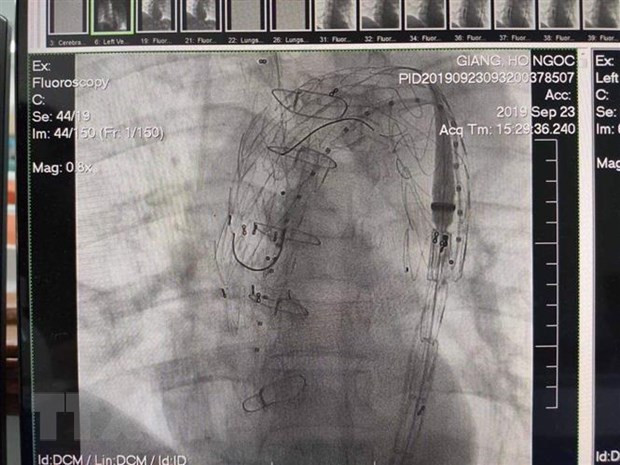

Kết quả can thiệp đặt stent graft động mạch chủ của bệnh nhân. (Ảnh: Mai Trang/TTXVN) |